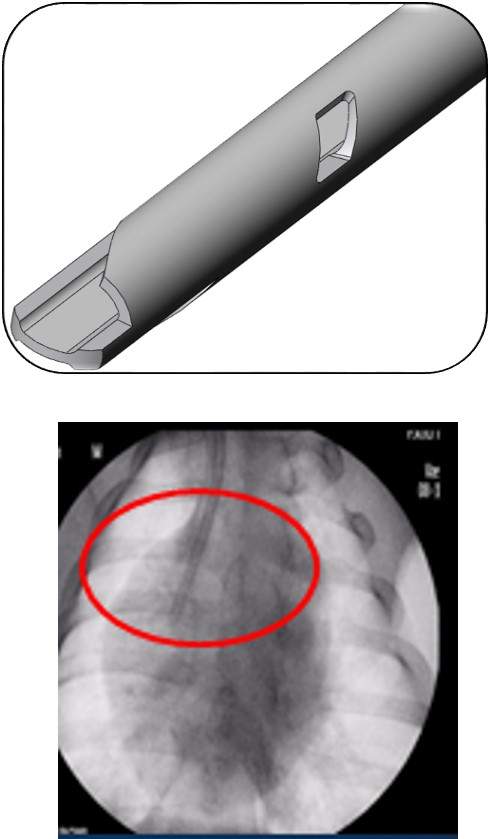

Перманентные (долговременные) катетеры для гемодиализа PALINDROME (Палиндром)

Гемодиализные катетеры PALINDROME (Палиндром) предназначены для высокоточного долгосрочного сосудистого доступа.

Изготовлены из материала Carbothane (Карботан), который представляет собой комбинацию полиуретана с углеводороными волокнами. Это обеспечивает большой внутренний просвет катетера в сочетании с высокой устойчивостью к перегибам.

Атравматичный наконечник облегчает установку катетера и минимизирует риск травмы сосуда

Уникальные боковые прорези вырезаны лазером, что делает их абсолютно гладкими и снижает риск позиционной окклюзии и вероятность тромбообразования.

Симметричная конструкция наконечника снижает показатель рециркуляции крови до 1%

Позволяет лечащему врачу различить функциональный наконечник катетера и визуализировать точное расположение наконечника в правом предсердии.